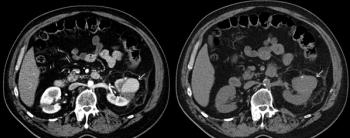

A 50-year-old man undergoes CT examination for workup of hematuria and abdominal pain. Noncontrast and postcontrast images from the CT are shown. What is your diagnosis?